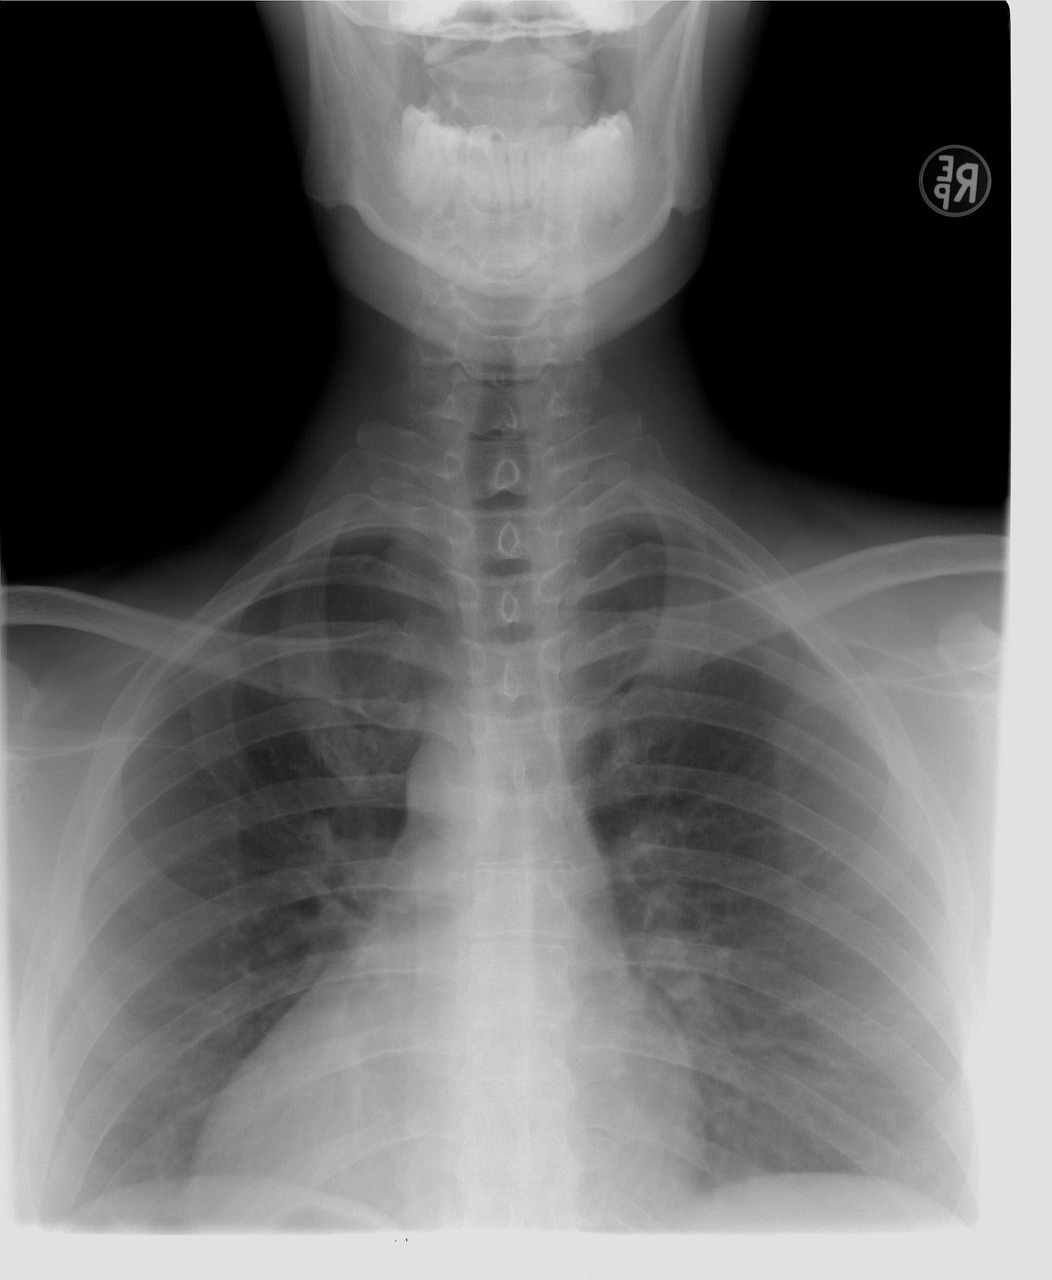

- 흉부 방사선 검사: 폐에 염증이 있는지 확인하는 방법으로 정확한 진단을 위해 사용합니다.